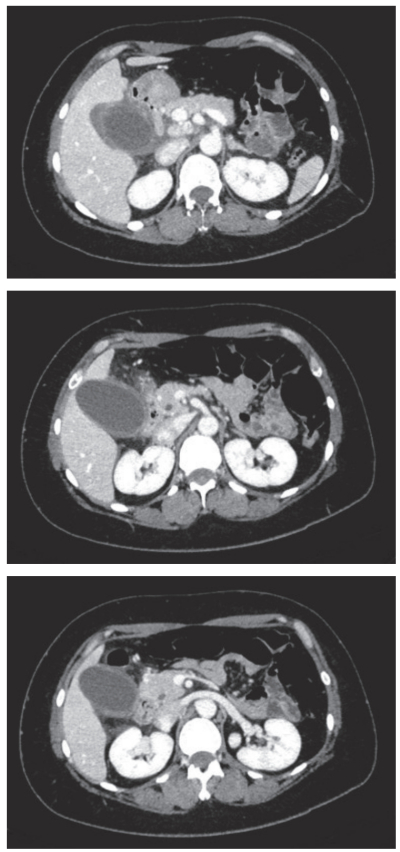

血液所見:赤血球 490万、Hb 15.9 g/dL、Ht 45%、白血球 14,500、血小板 19万。血液生化学所見:総蛋白 6.6 g/dL、アルブミン 3.9 g/dL、総ビリルビン 0.9 mg/dL、AST 32 U/L、ALT 46 U/L、LD 143 U/L(基準 120~245)、ALP 112 U/L(基準38~113)、γ-GT 128U/L(基準8~50)、アミラーゼ 54 U/L(基準 37~160)、尿素窒素 13.5 mg/dL、クレアチニン 0.7 mg/dL、血糖 166 mg/dL、Na 137 mEq/L、K 3.6 mEq/L、Cl 103 mEq/L。CRP 1.4 mg/dL。来院時の腹部造影CTを別に示す。

診断はどれか。

b. 急性胆嚢炎